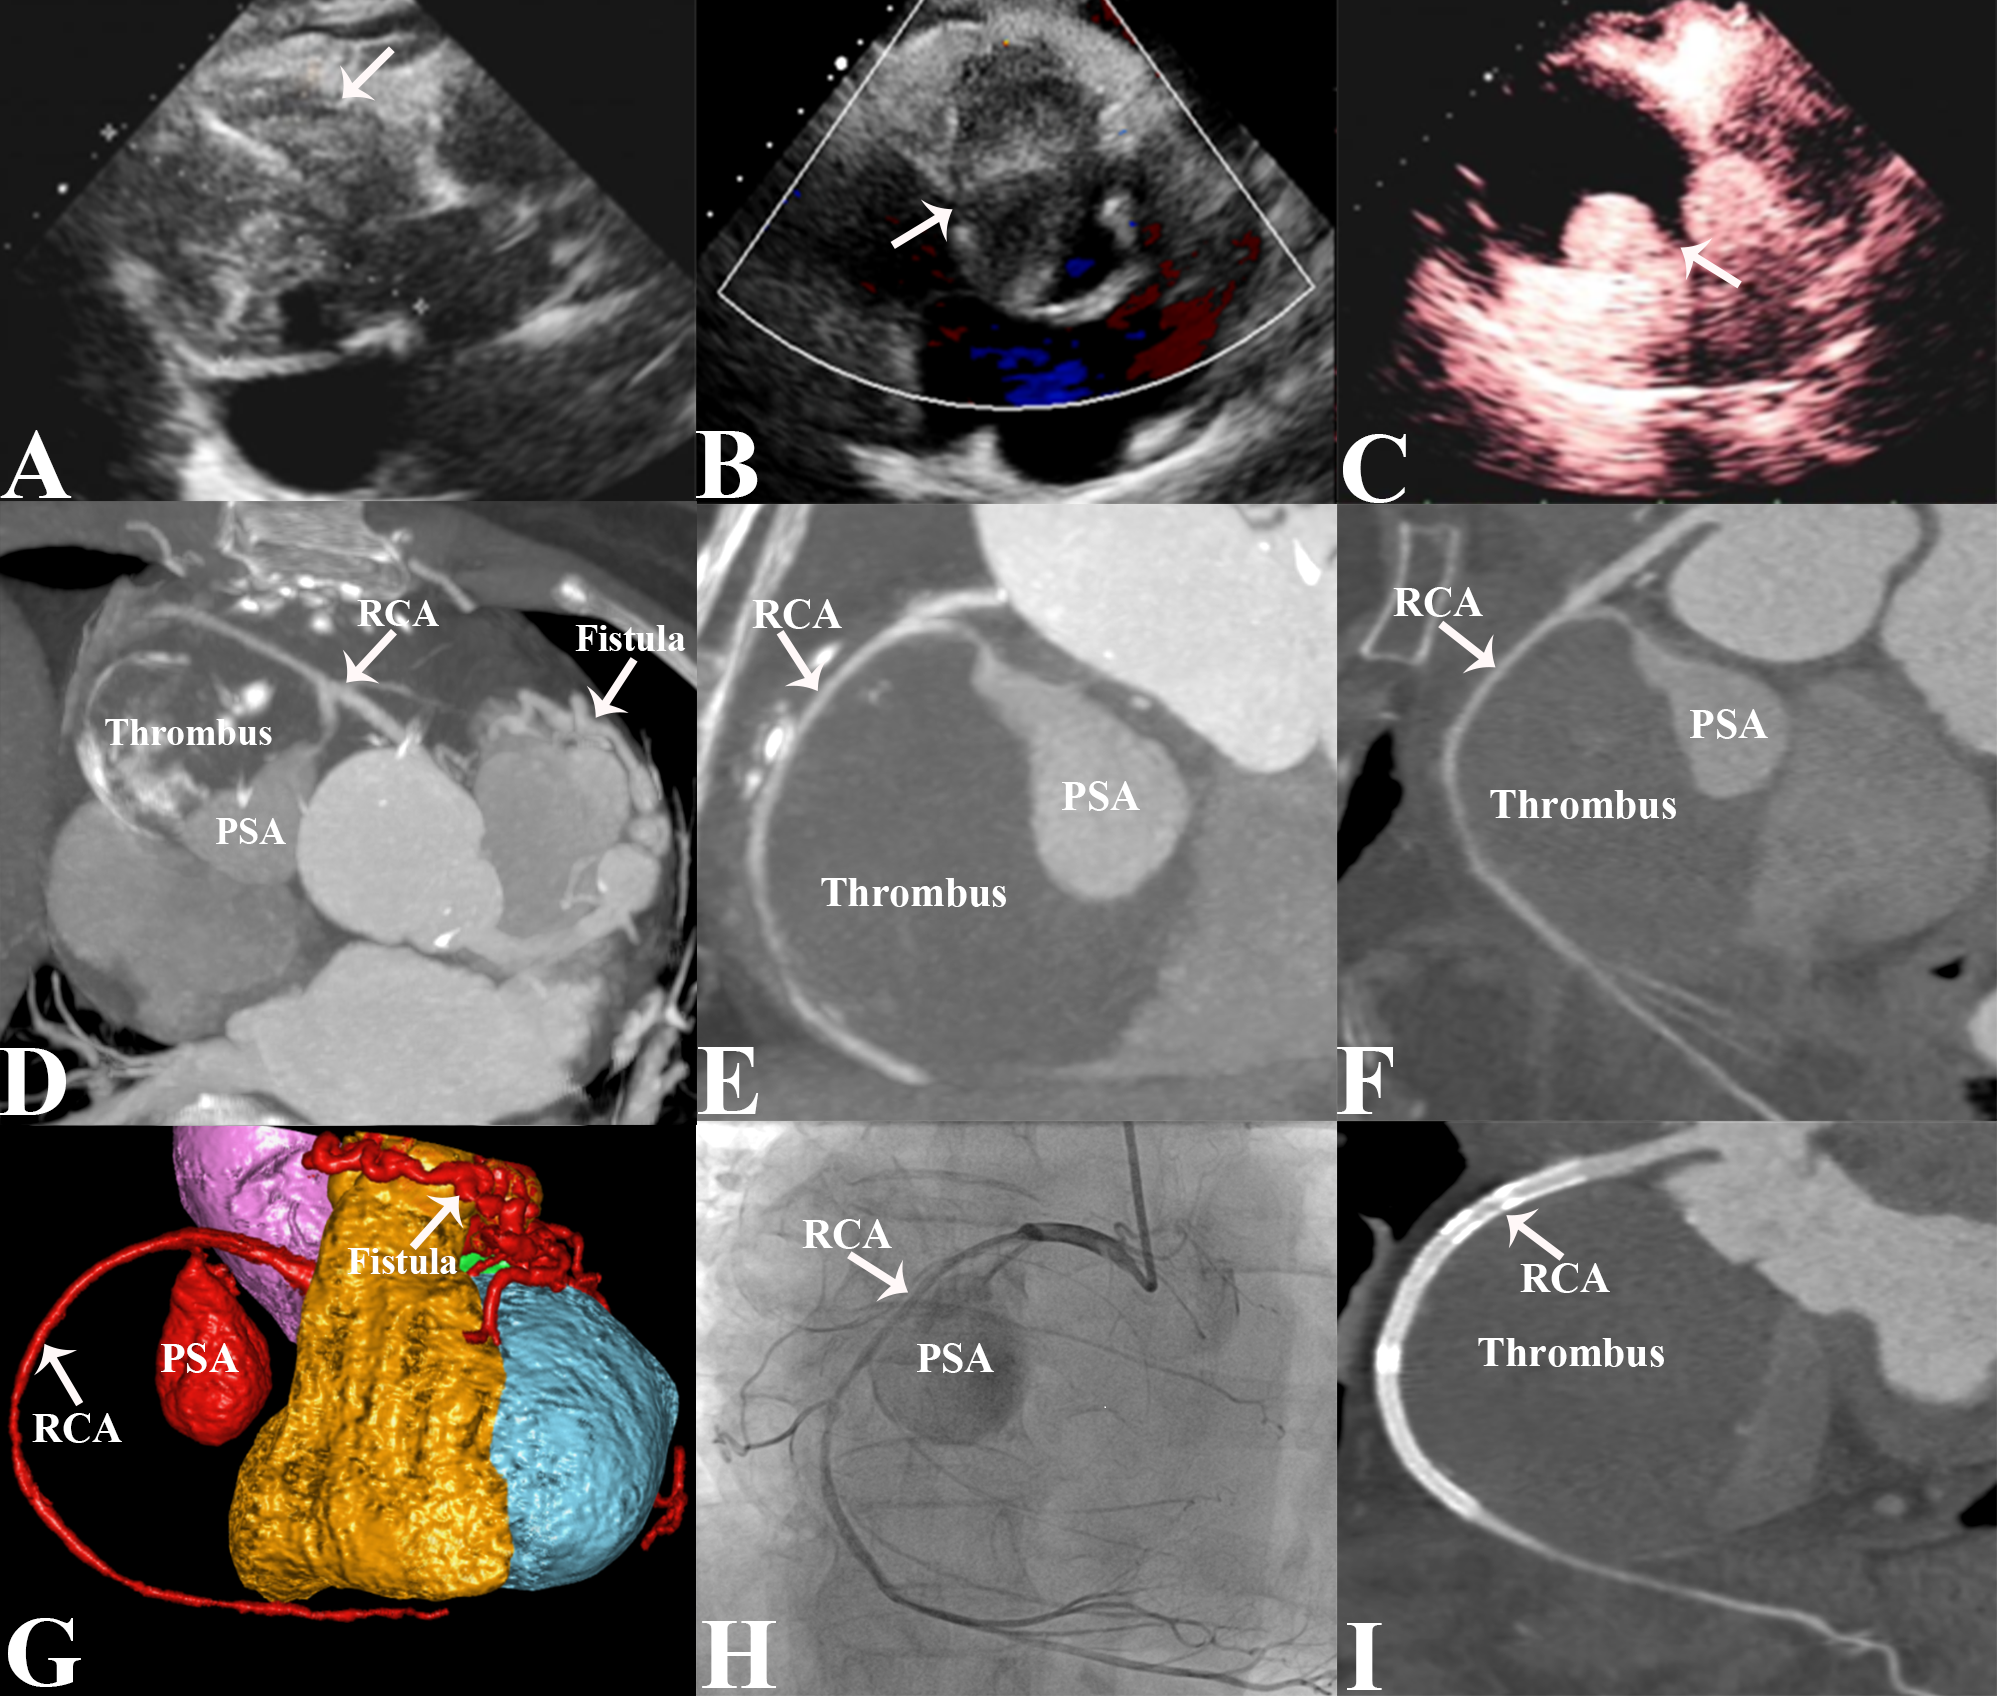

An 80-year-old woman presented with intermittent dizziness and discomfort for 1 month. Electrocardiogram revealed atrial flutter, with bidirectional or inverted T-wave in leads II, III, aVF, and V2-V6. Transthoracic echocardiography (TTE) revealed a hyperechoic and heterogeneous mass with anechoic areas in the right atrioventricular groove (Figure A). Color Doppler blood flow imaging showed no obvious blood flow signal within the mass (Figure B). Left ventriculography demonstrated a filling defect of the solid structure of the mass and contrast agent filling in the anechoic area (Figure C). Computed tomographic angiography (CTA) revealed bilateral coronary artery-pulmonary artery fistulas and a giant pseudoaneurysm (PSA) in the proximal segment of the right coronary artery (RCA), with massive mural thrombus and eggshell calcification at the edge, which compressed the right heart chambers and right coronary artery (RCA) (Figure D-F). A volume-rendering CTA image provided an intuitive view of the PSA with the coronary fistulas (Figure G). Coronary angiography (CAG) revealed the PSA arising from the proximal RCA with severe stenosis of RCA (Figure H, Video).

The patient underwent a percutaneous procedure using 3 overlapping Firebird drug-coated stents sized 2.75 x 33mm, 3.0 x 33 mm, and 3.5 x13 mm (MicroPort), and a polytetrafluoroethylene-covered coronary stent sized 3.5 x 18 mm (Lepu Medical Technology Co., Ltd.) Postoperative CTA demonstrated that the aneurysm was completely thrombosed with no leakage (Figure I). The post-procedural course was uneventful, and the patient was discharged after 4 days. At the 6-month follow-up, the patient remained asymptomatic.